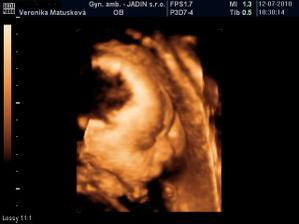

Adamko - 3D/4D

No tot vidno, že je náš syn, sa hanbil a hanbil až sa ukazovať nechcel....ale niekedy sa to podarilo, aj ked to nie je nejaká sláva. Pán doktor nám potvrdil chlapčeka, tak sme radi, vajká ukazoval ako len vedel len toho pipíka stále schovával. Ale je to za nami, pán doktor nás pekne popísal čo je kde, poodmeral nás a povedal, že je všetko v poriadku.